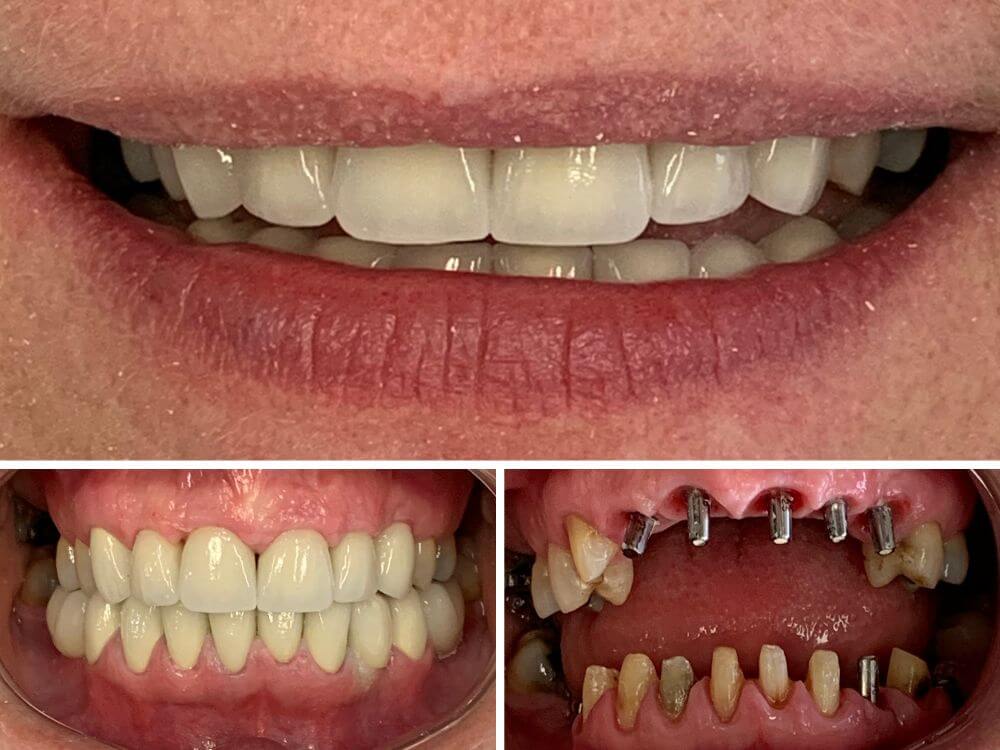

Hoje, sinto orgulho dos inúmeros casos de reabilitação oral e odontologia estética bem-sucedidos realizados em pacientes de toda a região de Santa Rosa/RS. Com tecnologia de última geração e materiais de alta qualidade, minha abordagem é completamente personalizada, visando sempre superar as expectativas dos meus pacientes.

Empregamos técnicas avançadas de implante dentário. Em alguns casos é possível concluir todo o tratamento em apenas 1 ou 2 consultas. Oferecemos um procedimento rápido, indolor e seguro para que você possa ter todos os seus dentes fixos novamente.

Implantes e a prótese são instalados no mesmo dia. Resultados estéticos e funcionais rápidos. Em até 72 horas, seu sorriso é completamente reconstruído.

Tratamento que exige um planejamento altamente eficaz em casos complexos. Visa a reposição de múltiplos dentes perdidos utilizando implantes dentários.